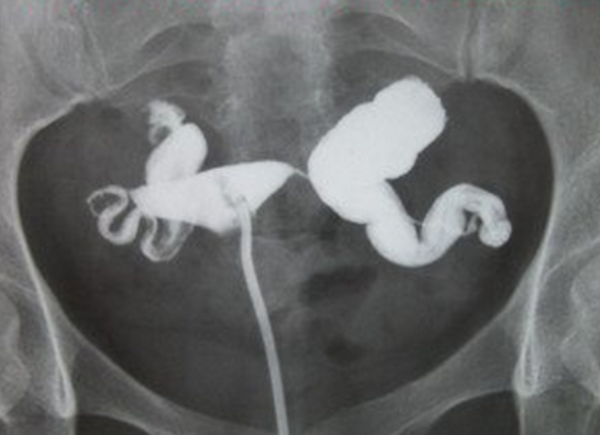

輸卵管積水對進行試管嬰兒有明顯影響。輸卵管積水也是必須要進行試管嬰兒才能懷上孩子,臨床研究資料表明,輸卵管積水患者試管嬰兒的成功率會下降50%,而流產率會增加2倍以上,宮外孕的概率明顯增加,因此在胚胎移植前應積極處理輸卵管積水。具體影響包括:

做試管嬰兒輸卵管積水需要切除的,否則會影響到試管的成功率。切除術可以在腹腔鏡下進行手術操作。是一種成熟的微創手術,適用於輸卵管積水比較嚴重的患者。是體外受精-胚胎移植(IVF-ET)前預處理輸卵管積水的首選方法。如果不切除的話,那麼做試管就有以下這些影響: